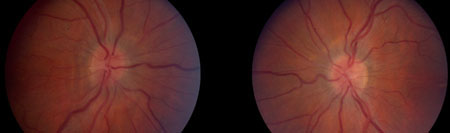

Hipertensão intracraniana idiopática

Inchaço estabelecido bilateral do disco

Do acervo pessoal do Dr. M. Wall; usado com permissão